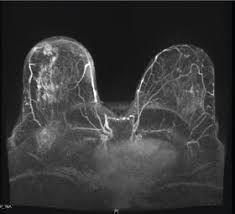

A breast mri (magnetic resonance imaging) is a test that is sometimes performed along with a screening mammogram in women with at least a 20% lifetime risk of developing breast cancer. Learn about getting a mammogram. Before the test, you may need to have a contrast solution (dye) injected into your arm through an intravenous line. But radiologists can still see signs of cancer. But not every woman who has been diagnosed with breast cancer needs a breast mri. This is considered an abnormal mammogram, but not necessarily one that's indicative of cancer. Ultrasound is useful for looking at some breast changes, such as lumps (especially those that can be felt but not seen on a mammogram) or changes in women with dense breast tissue. Calcifications are tiny flecks of calcium — like grains of salt — in the soft tissue of the breast that can sometimes indicate the presence of an early breast cancer.

Any area that does not look like normal tissue is a possible cause for concern. Dense breast tissue appears solid. It can also be used to investigate breast problems, such as a suspicious lump or thickening. Magnetic resonance imaging (mri) of the breast — or breast mri — is a test used to detect breast cancer and other abnormalities in the breast. Imaging and lobular breast cancer. It also can be used to look at a suspicious area that was seen on a mammogram. A 3d mammogram is used as a breast cancer screening test to look for breast cancer in people with no signs or symptoms of the disease. However, advances in mammography, ultrasound, and magnetic resonance imaging present opportunities to improve the diagnosis and preoperative assessment of ilc. Lobular breast cancer can be more difficult to see on imaging and scans. This is acceptable for diagnostic exams. A lump or tumor will show up as a focused white area on a mammogram. In this mammogram image, the breast calcifications are in ductal patterns. Breast imaging specialists like dr.

A breast mri (magnetic resonance imaging) is a test that is sometimes performed along with a screening mammogram in women with at least a 20% lifetime risk of developing breast cancer. Finding breast lumps and seeing change in the size and shape. There are different kinds of asymmetries, from difference in size to tissue density. Ductal carcinoma in situ is usually seen as linear microcalcifications (see arrows), which demonstrate linear orientation, as seen in this patient. A breast mri usually is performed after you have a. This type of cancer precedes the development of a distinct mass, lump or invasive cancer. A screening mammogram is performed at regular intervals to check for breast cancer in women who have no signs or symptoms of the disease. The person operating the ultrasound will sweep, or fan, the probe back and forth to look at different areas in 90 degree angle images. These images are called mammograms. On a mammogram, an asymmetry typically means there's more tissue, or white stuff on the mammogram, in one area than on the opposite side. Imaging and lobular breast cancer. Breast mri is sometimes used in women who already have been diagnosed with breast cancer, to help measure the size of the cancer, look for other tumors in the breast, and to check for tumors in the opposite breast. Breast imaging specialists like dr.